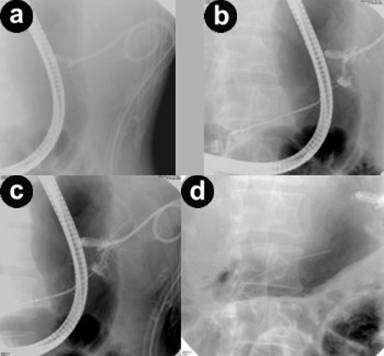

Of the four patients with external pancreatic fistula, three had partial disruption and one had complete disruption of the main pancreatic duct. All four patients had single disruption of the main pancreatic duct. The site of pancreatic duct disruptions was head, body and tail in two, one and one patient, respectively. One patient with partial disruption in the body had a complex fistula (pancreaticocutaneojejunal fistula) following surgical necrosectomy. In patients with partial disruption a bridging 5-Fr nasopancreatic drain was placed in one patient and bridging 7-Fr stents were placed in other two patients. All three patients had resolution of external pancreatic fistula within 6 weeks and there has been no recurrence over a follow up of 12 to 36 months (Figure 2). Even patient with complex fistula had complete resolution. The ductal disruption was also documented to be healed in these patients on nasopancreatic drain gram or ERCP. In one patient with complete disruption, a non bridging 7-Fr stent was placed. However, in this patient there was no resolution of external pancreatic fistula even after 8 weeks of drainage and was successfully treated surgically.

Figure 2. a. Post-traumatic external pancreatic fistula. A percutaneous drain noted. b. Pancreatogram shows partial disruption at tail end. c. Guide wire negotiated across the disruption. d. A 7-Fr stent placed across the disruption. |